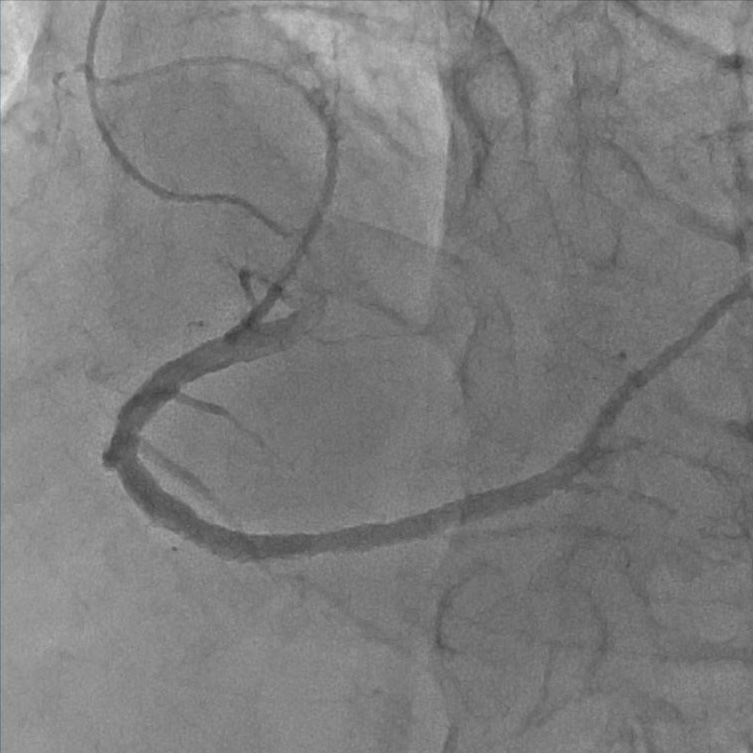

血管造影室:Alphenix (Canon)

血管造影装置は、X線TV室で使用している装置同様、X線を使ってリアルタイムで体内の情報を確認しながら手術を行う際などに使用する装置です。X線TV室と異なるのは血管造影に使用する点で、装置を動かすことによって患者さんの体の向きを変えずに、さまざまな方向から見れるような作りになっています。

血管造影とは、カテーテルと言われる細い管のようなものを、手首または足の付け根の動脈から血管内に挿入して、目的部位まで進め、造影剤を注入することで血管が描出されます。

放射線技師は主に装置の管理や画像の管理、被ばく線量の管理をしています。

- 当院での主な使用 ・心臓の血管の検査・治療(心臓カテーテル検査・治療)

・下肢血管の検査・治療